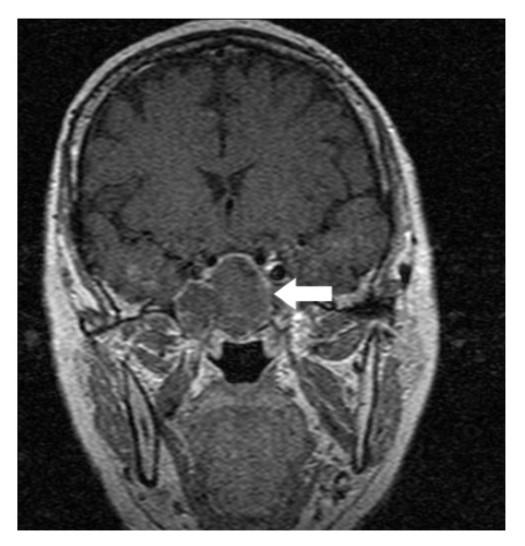

A 64-year-old lady presented to the outpatient department with complaints of headache and right eye blurring of vision for one month. Neurological examination revealed that bitemporal hemianopsia and impairment of visual acuity. Findings from fundus examination were within normal limits. Rest of the brain appeared unremarkable. Endocrine evaluation was normal. Results of renal function tests, liver function tests and haemogram test were within normal limits. A clinical diagnosis of non-secretory pituitary adenoma was made. Magnetic resonance imaging showed a well-circumscribed contrast-enhancing lesion in the sella (Figure 1, Figure 2). The patient underwent an endoscopic endonasal/transsfenoidal surgery in the supine position and total lesion resection was peformed. Intraoperatively, the lesion was found to be yellow colour, soft and avascular and it was removed totally until the sella turcica was visualized (Figure 3).In histopathologic examination septate hyphae were observed between inflammatory cells, Grocott staining is positive, but acid-fast stain for acid-fast bacilli (AFB) was negative. Histopathological findings suggest that infection of Actinomyces (Figure 4, Figure 5). We performed to patient consulted by patients to infectious diseases clinic. Patients underwent intravenous 6x2 gr ampicillin for four weeks.Then oral 4X500 mg amoxicillin treatment is planned a for at least 6 months. Patient did not have any deficits in the next six months.

Figure 2.White arrow shows on coronal section of MRI that a well-circumscribed contrast-enhancing lesion in the sella